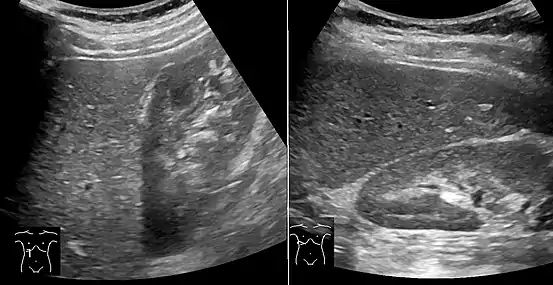

On X-ray computed tomography (CT), the increased fat component will decrease the density of the liver tissue, making the image less bright. Typically the density of the spleen and liver are roughly equivalent. In steatosis, there is a difference between the density and brightness of the two organs, with the liver appearing darker.[12] On ultrasound, fat is more echogenic (capable of reflecting sound waves). The combination of liver steatosis being dark on CT and bright on ultrasound is sometimes known as the flip flop sign.

On abdominal ultrasonography, steatosis is seen as a hyperechoic liver as compared to the normal kidney.